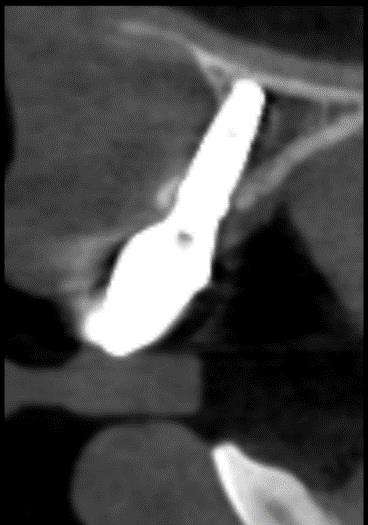

Fig. 1: Implant Missing Bone on Outside Surface

When a dental implant is missing bone on its buccal (outside) surface, it will continue to lose support and become loose, leaving a large defect. In many cases, however, it can be saved using meticulous techniques.

Case Type I: Bone loss on the outside surface of an implant can be reversed with precise detoxification and bone grafting.